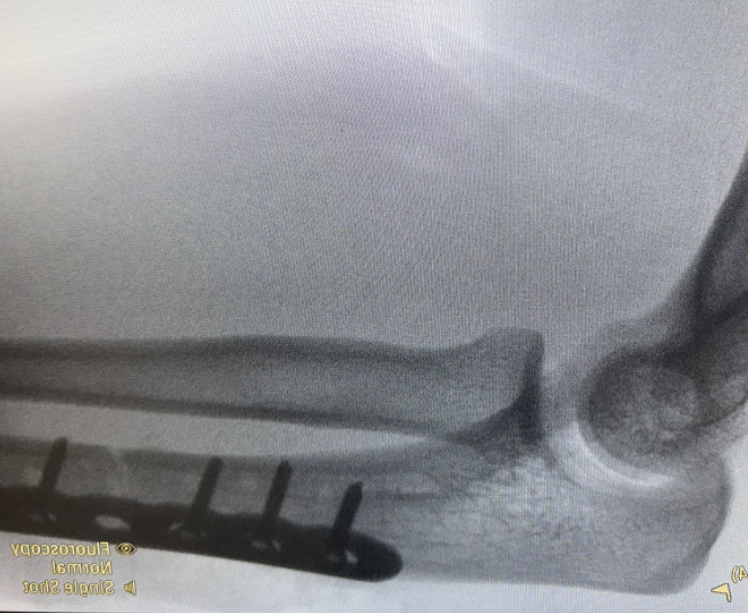

Ongoing anterior radial head dislocation after olecranon plating, treated with lateral approach and open reduction